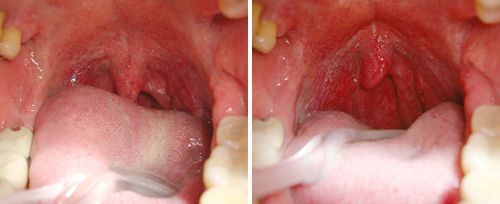

Liệu pháp NightLase® của Fotona là điều trị laser thân thiện với bệnh nhân nhằm tăng cường chất lượng giấc ngủ của người được điều trị. NightLase® có thể giảm bớt hậu quả và biên độ ngáy bằng một điều trị laser nhẹ nhàng tác dụng lên mô niêm mạc.

Phương thức phát xung laser độc quyền của Fotona tối ưu hóa độ dài các xung, giúp làm nóng mô niêm mạc miệng một cách an toàn. Cách làm này đủ nhẹ nhàng để sử dụng trên các mô nhạy cảm trong miệng, nhưng cũng đủ mạnh để tạo hiệu quả làm nóng về mặt lâm sàng.

Với các thực hành NightLase® đã qua đào tạo bài bản, việc tạo ra thay đổi tích cực về giấc ngủ có tỷ lệ thành công cao. Các nghiên cứu đã cho thấy NightLase® có thể làm giảm và làm yếu đi tình trạng ngáy và cung cấp cách thức giảm ngáy hiệu quả, không xâm lấn.